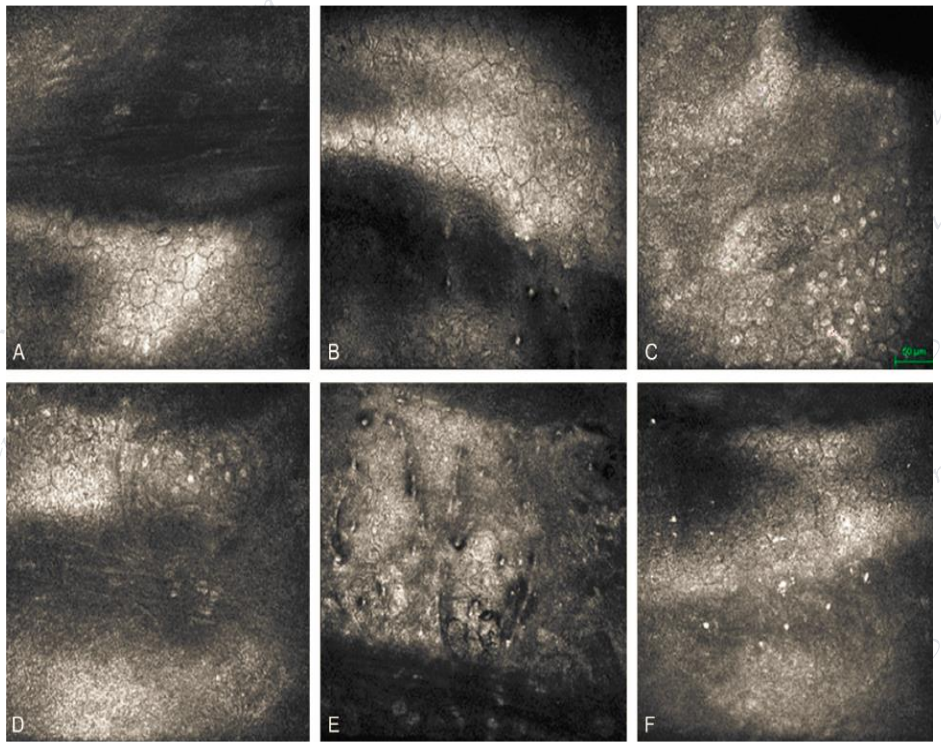

图片

图18.PPCD典型病例:典型双轨征